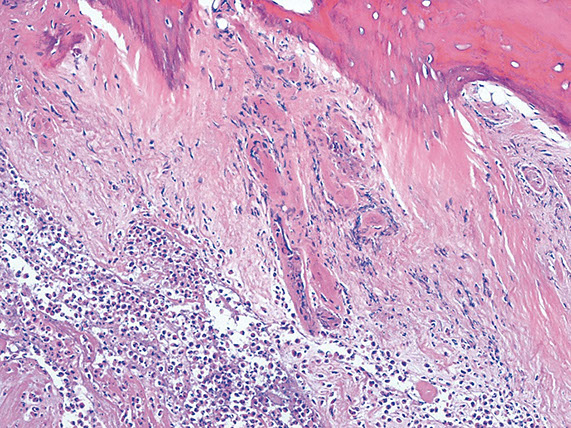

Hyperparathyroidism - Brown tumors. Right image shows zone of bone resorption in center c defect filled c fibroblastic tisuue, and around the periphery is osteoid-producing area that looks like fibrous dysplasia. Image on left is close of area replacing fibroblastic tissue c lots of osteoclast-like GCs, that may lead to misdiagnosis of giant cell tumor (except GC tumors usually lack fibrogenic stroma)

Brown Tumor

Bone loss causes microfractures and hemorrhage causing macrophage influx and reparative fibrous tissue

Brown from vascularity, hemorrhage and hemosiderin deposition

"Brown tumors" of bone are caused by hemorrhage and hyperparathyroidism

- may also be caused by pseudohyperparathyroidism, but is usually due to parathyroid adenoma, hyperplasia, or rarely carcinoma or chronic renal failure

Micro: Osteoclasts line cystic spaces (tunneling), which also have a very fibrous stroma, inc formation of woven bone, and peritrabecular fibrosis, MNGCs